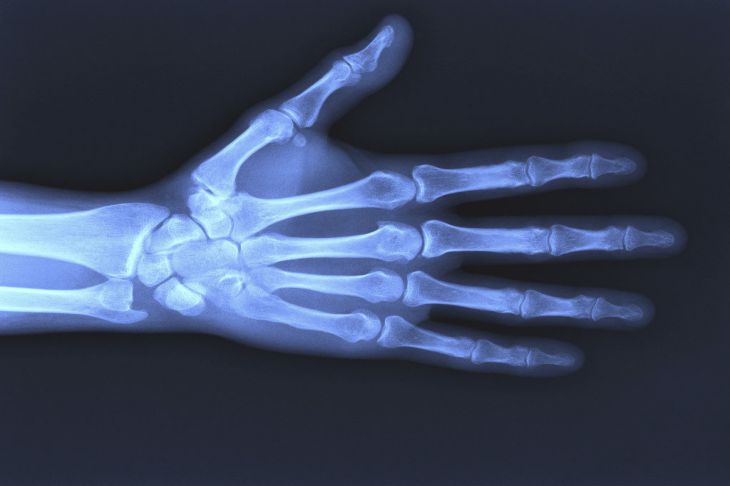

Немецкий физик Вильгельм Конрад Рентген 8 ноября 1895 года во время эксперимента подал ток в катодную трубу, запечатанную толстым черным картоном. Рядом случайно оказался экран из бумаги, покрытый кристаллами бария.

Экран светился зеленым цветом во время подачи тока.

Исследуя это явление детально, ученый обнаружил, излучение способно проходить через прозрачные материалы, не преломляясь и не отражаясь от них.

Позже ученый сделал первый рентген-снимок кисти руки своей жены.